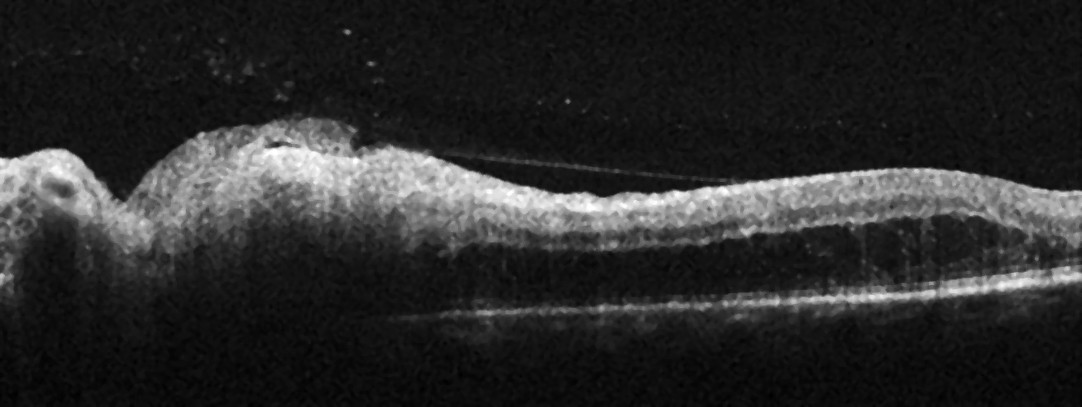

Optisk koherens-tomografi (OCT) av den venstre papillen viste fortykkelse av det peripapillære retinale nervefiberlaget med en gjennomsnittstykkelse på 159 µm (> 95 % referanseintervall) (figur 2). Man så også en fortykkelse av de indre retinale lagene svarende til det temporale infiltratet.

De retrobulbære smertene forsvant etter få dager. Etter én ukes behandling opplevde pasienten også en viss bedring av synet, og beste korrigerte visus var 0,8. Ved undersøkelse forelå fortsatt noen celler i glasslegemet. Infiltratet temporalt for papillen var litt mindre og skarpere avgrenset. Det ble gitt en ny intravitreal injeksjon med klindamycin. Etter ytterligere én ukes behandling var beste korrigerte visus 1,0. Infiltratet var blitt enda mindre, og optisk koherens-tomografi (OCT) viste normalisering av det peripapillære retinale nervefiberlaget, med gjennomsnittstykkelse 118 µm (innenfor 95 % av referanseintervallet). Det ble gitt en tredje og siste intravitreal injeksjon med klindamycin.